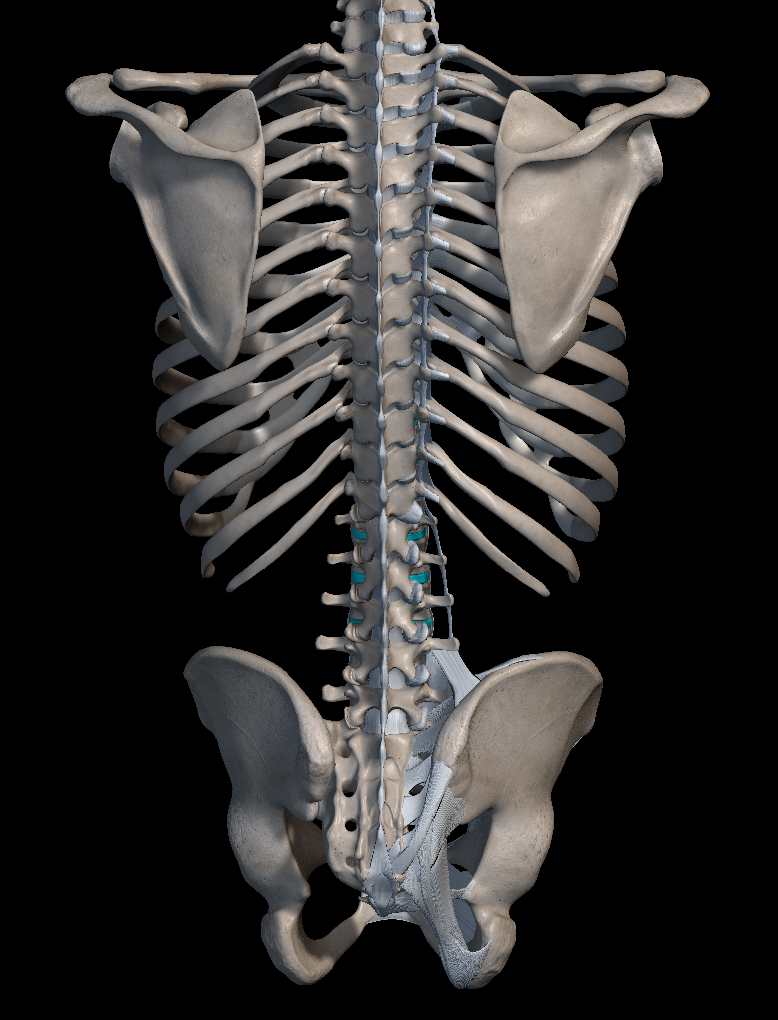

강직성 척추염은 주로 척추, 특히 꼬리뼈 부위의 천장 관절 쪽에 영향을 미치는 만성 관절염의 일종이지만 경우에 따라 다른 관절에도 영향을 미치곤 합니다.

'강직성 척추염'은 명칭 그대로 허리 부위에 염증이 생겨 움직임이 둔해지는 병이라고 생각하시면 됩니다. 하지만 척추의 유연성과 가동 범위에 제한이 걸리면서 어깨, 무릎, 발목 등의 다른 관절에도 통증을 일으키곤 하지요.

종종 드물게 강직성 척추염으로 인한 심각한 관절 손상이나 신체 변형을 해결하기 위해 수술이 필요한 경우도 있습니다. 여기에는 관절 치환 수술이나 척추 융합 수술 등이 주로 포함됩니다.